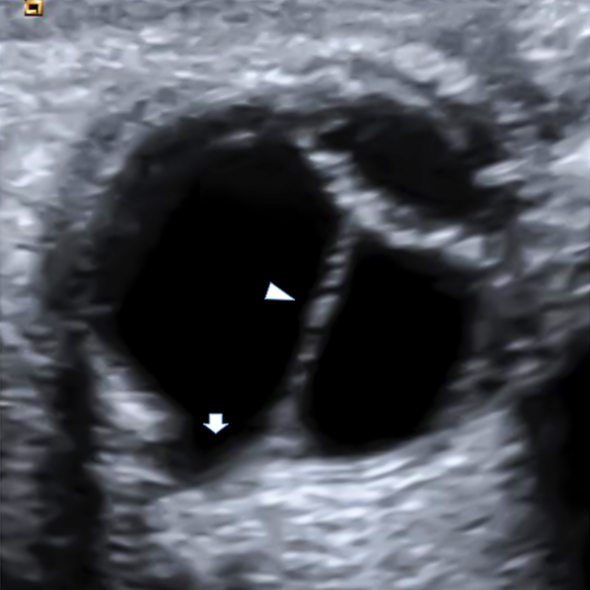

Doppler ultrasonography imaging showed a shortened axial length, cataract, a retrolental vascularized mass extending from the optic disc to the posterior lens capsule, and depression and enlargement of the optic disc and surrounding tissue toward the posterior pole in the right eye (Figure 2 [Fig. 2]). No pathological findings were seen in the left eye.

Figure 2: Cataract, a retrolental vascularized mass extending from the optic disc to the posterior lens capsule, and depression and enlargement of the optic disc in the right eye by Doppler ultrasonography

Ultrasonography examination is essential for individuals who are uncooperative or unsuitable for fundus examination owing to media opacity [9]. As in the present study, Doppler ultrasonography is needed to establish the accurate diagnosis by demonstrating MGS with PHPV.